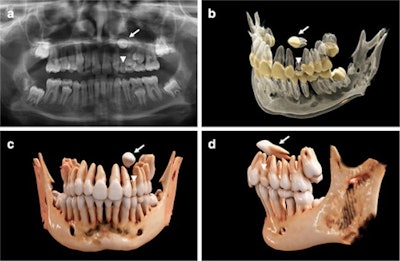

An 11-year-old girl with a horizontally impacted canine (white arrows) and a persisting deciduous canine (white arrowheads). (a) An x-ray of the girl's mouth. (b) Semitransparent reconstruction parameters are used to visualize bone, teeth, and different dental tissues. (c and d) The teeth and bone tissue with a soft kernel show a photorealistic visualization in both a frontal and lateral view.Recently, cinematic rendering, a technology that uses data derived from CT and conebeam CT images, has been used as an alternative approach for visualizing volumetric medical imaging data. Since its introduction, cinematic rendering has found applications in medical clinical research and anatomical education, but it has not been tailored to dentistry. Currently, there is only limited research on this technology in dentistry. Mainly, cinematic rendering has focused on fractures and carcinoma as maxillofacial indications, the authors of the report wrote.